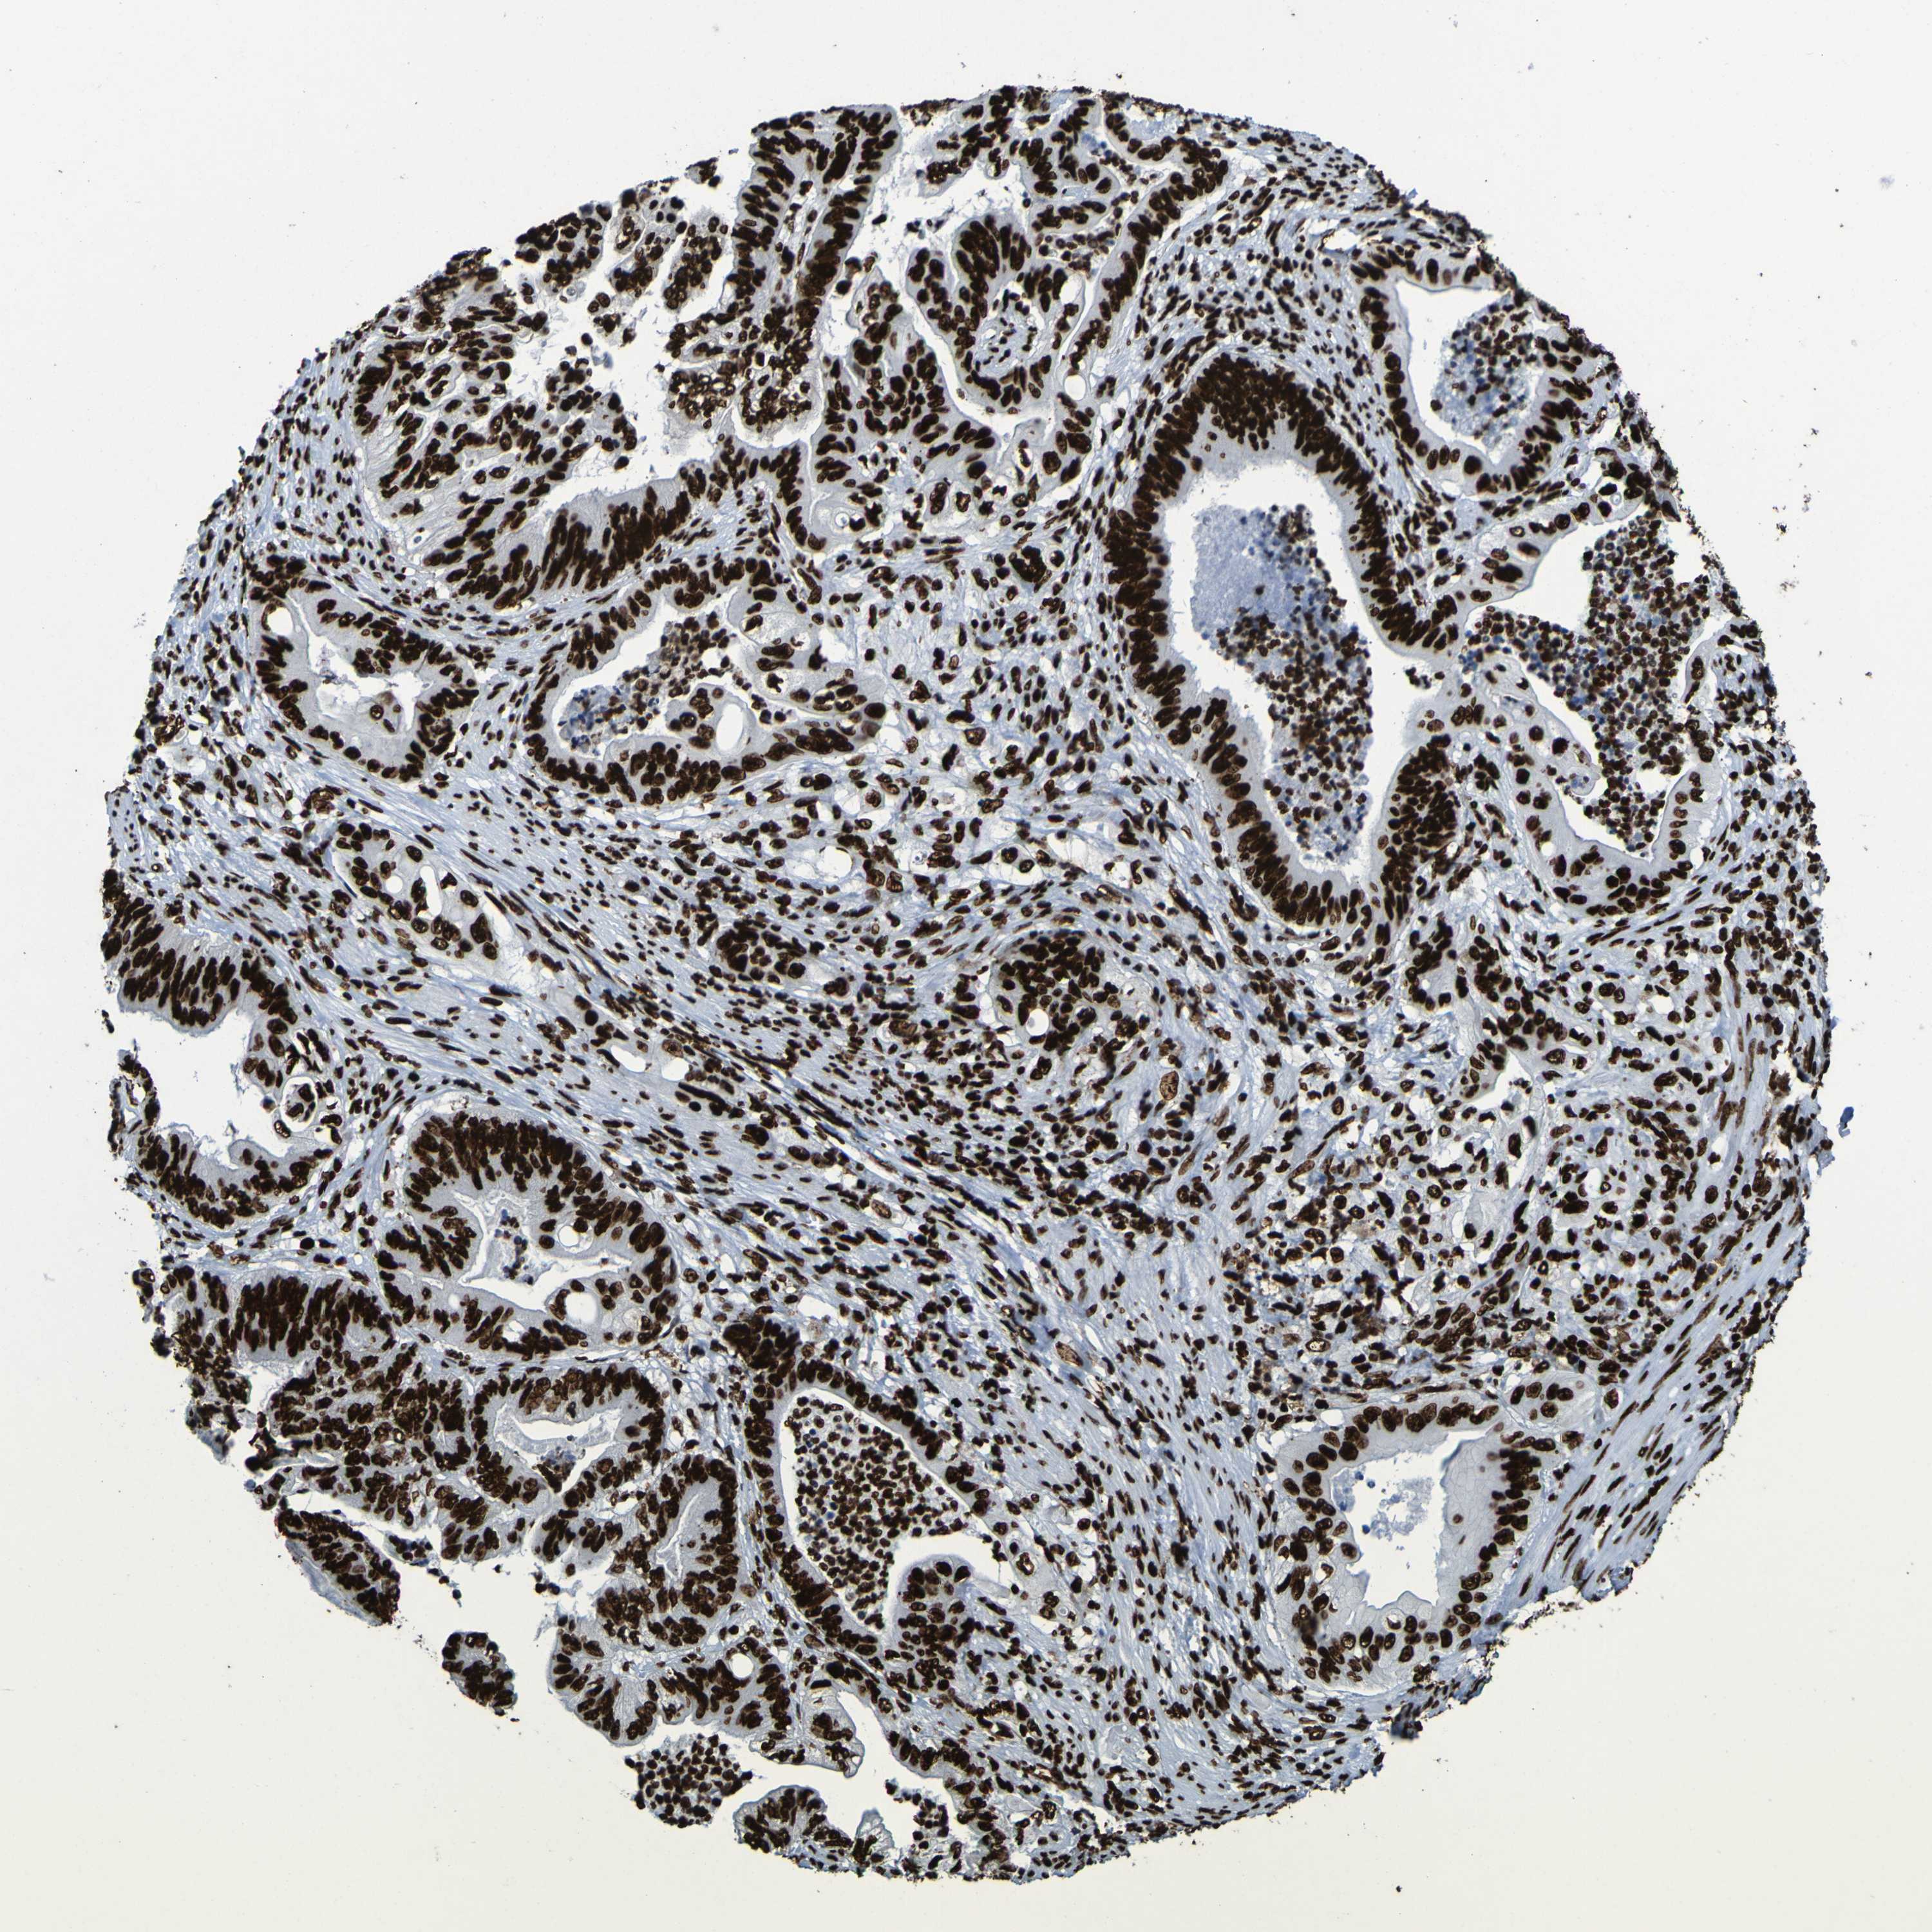

STOMACH CANCER - Protein expressioni

A mouse-over function shows sample information and annotation data. Click on an image to view it in a full screen mode. Samples can be filtered based on level of antibody staining by selecting one or several of the following categories: high, medium, low and not detected. The assay and annotation is described here.

Note that samples used for immunohistochemistry by the Human Protein Atlas do not correspond to samples in the TCGA dataset.

Antibody stainingi

Antibody staining in the annotated cell types in the current human tissue is reported as not detected, low, medium, or high, based on conventional immunohistochemistry profiling in selected tissues. This score is based on the combination of the staining intensity and fraction of stained cells.

Each image is clickable and will lead to virtual microscopy that enables deeper exploration of all samples and also displays staining intensity scores, fraction scores and subcellular localization as well as patient and tissue information for each sample.

Antibody HPA011384

Antibody CAB012983

Staining

High

Medium

Low

Not detected

Intensity

Strong

Moderate

Weak

Negative

Quantity

>75%

75%-25%

<25%

None

Location

Nuclear

Cytoplasmic/membranous

Cytoplasmic/membranous,nuclear

Adenocarcinoma, NOS

Adenocarcinoma, High grade